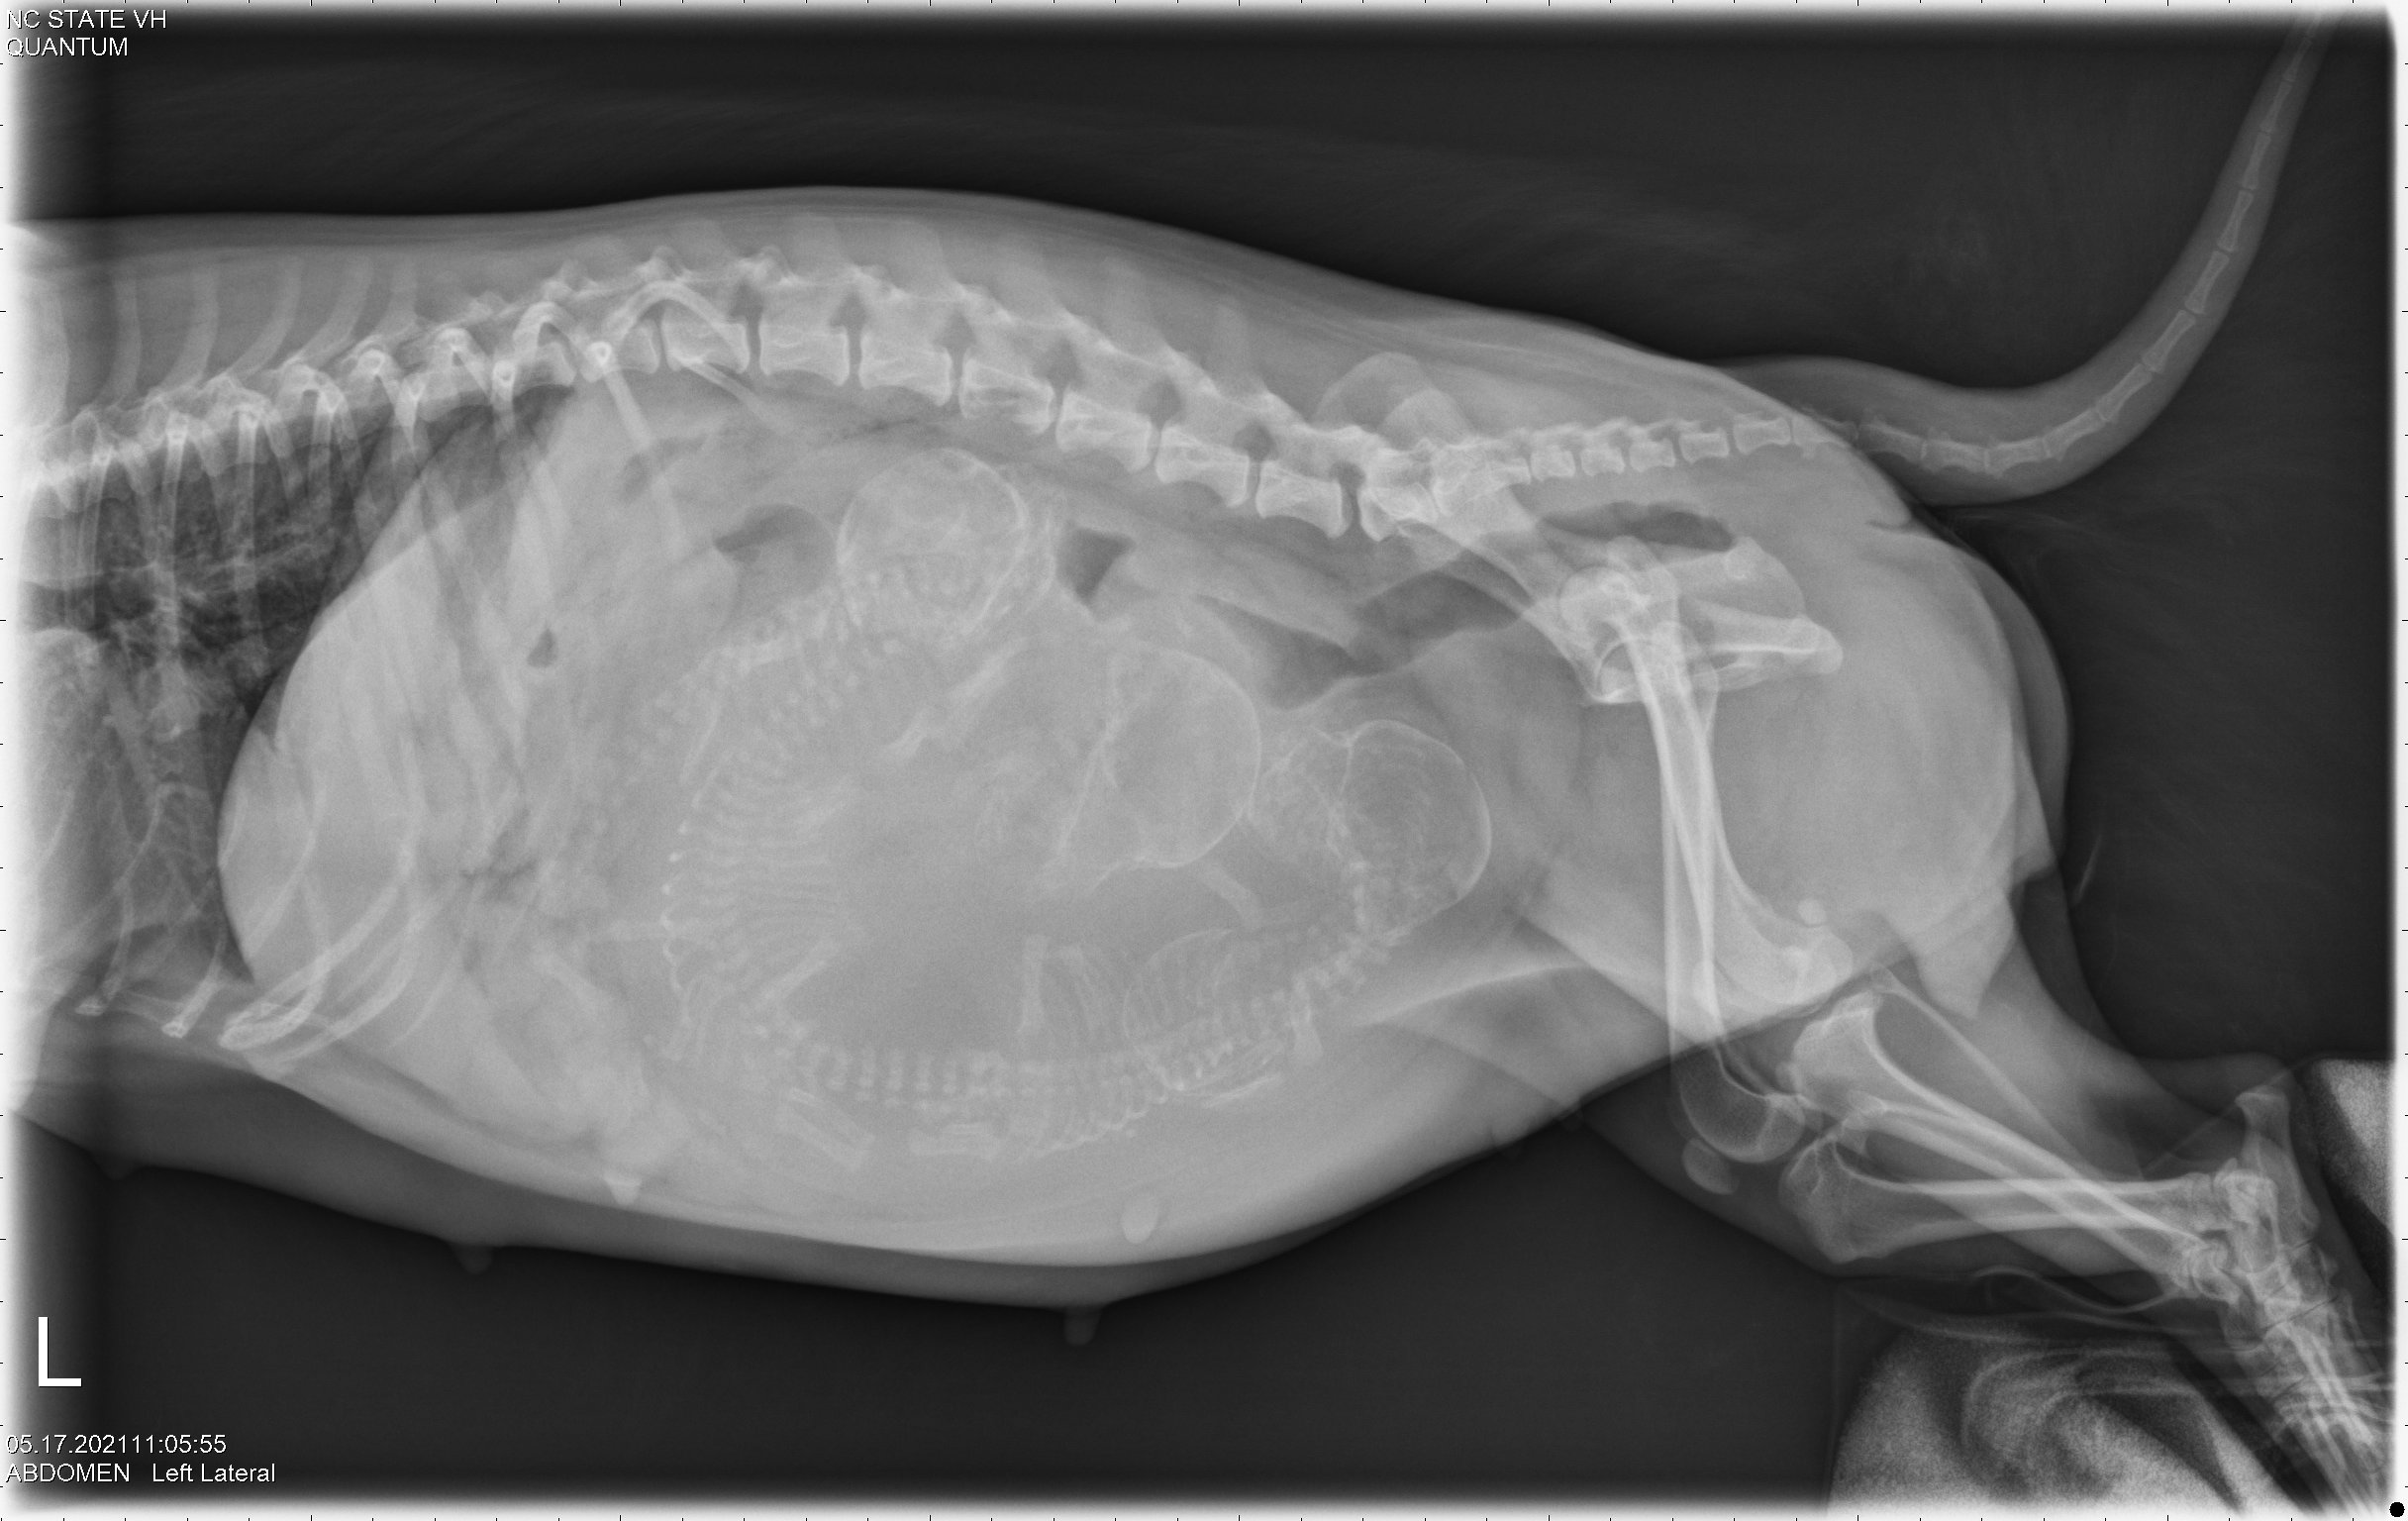

This morning we drove to NC State. X-rays (photo 1 and photo 2) confirmed that Siri has four puppies, and it looks like the puppies skulls are small enough that they will fit through Siri's pelvic canal. So trying for a free whelp is recommended. After taking the rest of my dogs to my petsitter, Siri and I moved into a hotel near the vet school.